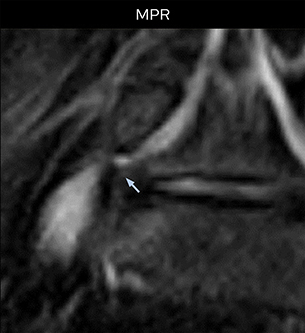

“Recently, the two surgical methods extreme and oblique lateral interbody fusion (XLIF and OLIF) have become mainstream for minimally invasive treatment of lumbar spinal canal stenosis and intervertebral foramen stenosis. With these surgical techniques, the spine is approached from the flank, and prior knowledge of the exact anatomy of the lumbosacral plexus would be extremely helpful. To that end, high slice resolution (less than 1 mm acquisition) that enables sharper sagittal MPR images will be needed.”

“For both brachial and lumbar plexus, we are currently using a 230 mm FOV and voxels of about 1 x 1 x 2 mm acquired (1 x 1 x 1 mm reconstructed). This provides us a good representation of the nerves, even though this FOV is relatively small. Regarding the inplane resolution, we hope to be able to bring that down to 0.7 mm, similar to our typical 2D multislice T2W images,” says Tanji.

“In such case, we would then browse through axial T2-weighted MR images slice by slice and mentally reconstruct the actual situation based on both radiculography and MRI. Fortunately, NerveVIEW can now very well show nerve courses and presence of nerve compression or edema in one single image series.” “We have often seen NerveVIEW directly depict details of the nerve compression that were not observed by radiculography. Therefore, we think that with NerveVIEW we can reduce the number of invasive examinations, especially for some patients with lumbar plexus symptoms.”

“For example, in sagittal images, when the presence of fat is observed in the intervertebral foramen, it suggests that there is a margin around the nerve. Similarly, the absence of fat indicates that the nerve is being compressed. So, we used to deduce nerve compression indirectly. With NerveVIEW, however, we can observe the condition of the nerves directly, regardless of the presence or absence of fat. We always prefer such direct observation of anatomy over having to make an inference about it.”